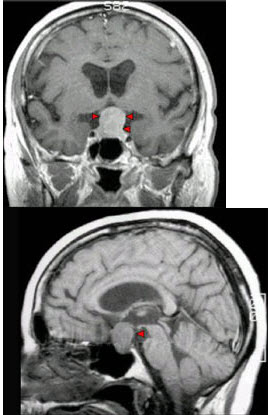

172、单项选择题

男,37岁,视力模糊,部分视野缺失,伴有头痛、恶心数月,MRI检查如图,最可能的诊断为()

A.颅咽管瘤

B.脑膜瘤

C.蛛网膜囊肿

D.垂体瘤

E.表皮样囊肿